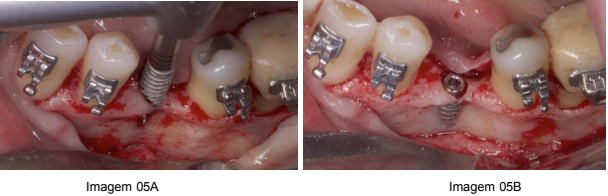

Durante a intervenção cirúrgica, foi instalado o implante dentário do tipo Cone Morse 3.5 x 9mm (Marca Implacil), com cuidado para garantir um bom posicionamento tridimensional no osso remanescente, criando uma boa base para a futura reabilitação. (Imagem 05A e Imagem 05B)

Fonte: próprio autor